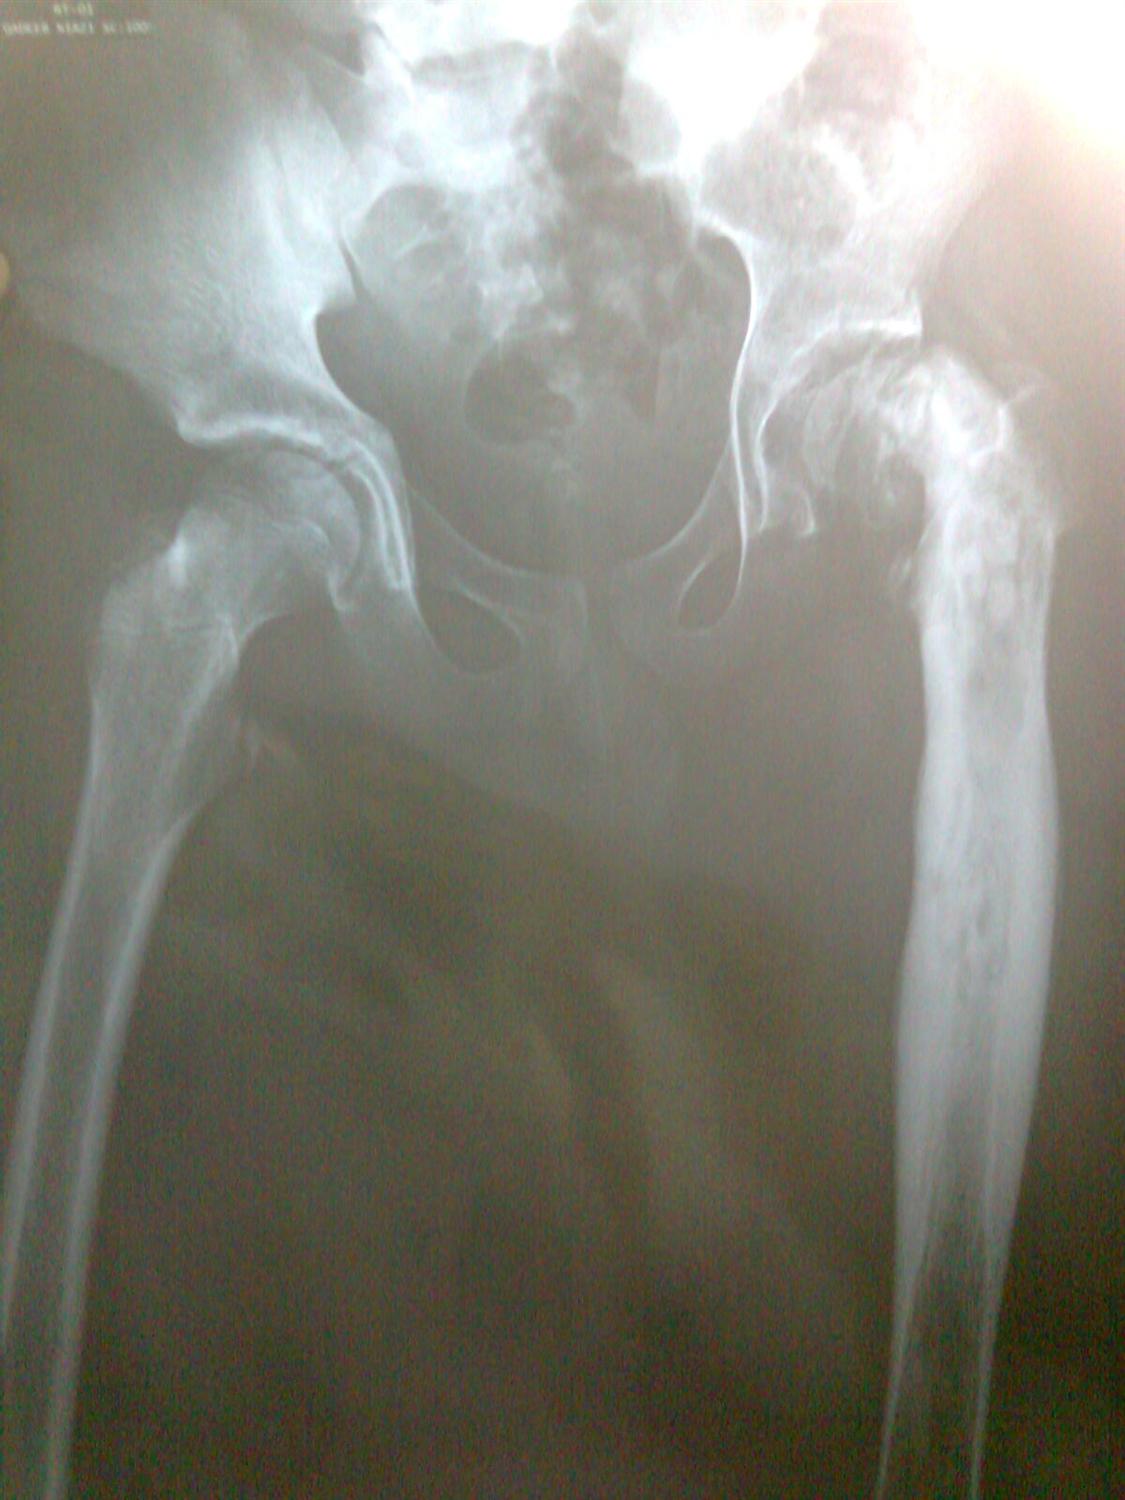

Radiographic progression of septic arthritis of the hip BMJ Case Reports

Radiographic progression of septic arthritis of the hip BMJ Case Reports Septic Arthritis In Hip Joint Treatment of bacterial septic arthritis in the native adult hip joint can be challenging. native joint infections most commonly occur in the knee, followed by the hip, shoulder, ankle, elbow, and wrist. if septic arthritis occurs in an artificial joint (prosthetic joint infection), signs and symptoms such as minor pain. septic arthritis is usually monoarticular involving one. Septic Arthritis In Hip Joint.

Ultimate Radiology Septic arthritis of hip joint Septic Arthritis In Hip Joint native joint infections most commonly occur in the knee, followed by the hip, shoulder, ankle, elbow, and wrist. However, polyarticular septic arthritis involving. treatment of bacterial septic arthritis in the native adult hip joint can be challenging. septic arthritis is usually monoarticular involving one large joint such as the hip or knee; septic arthritis is a. Septic Arthritis In Hip Joint.

From www.wikidoc.org

Septic arthritis x ray wikidoc Septic Arthritis In Hip Joint septic arthritis presents with a hot, swollen, acutely painful joint with restriction of movement. native joint infections most commonly occur in the knee, followed by the hip, shoulder, ankle, elbow, and wrist. if septic arthritis occurs in an artificial joint (prosthetic joint infection), signs and symptoms such as minor pain. septic arthritis is a rare and. Septic Arthritis In Hip Joint.